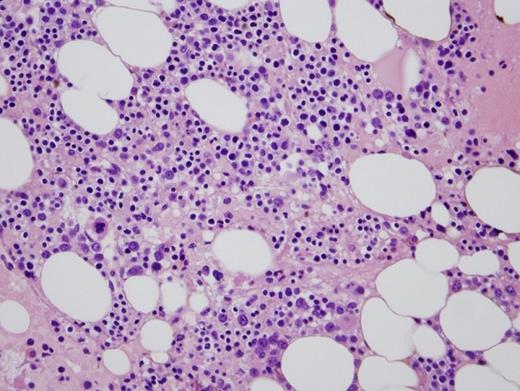

Bone marrow biopsy

In this case, the patient presented with peripheral cytopenia only following renal transplantation while on mycophenolate mofetil and tacrolimus (MMF/TAC) for immunosuppression. Congenital PHA and autoimmune disorders (options A and E, respectively) are highly unlikely with this clinical presentation. Leukopenia and PPHA caused by infection (option B) is possible, especially in the setting of immunosuppression. However, there was no evidence of infection after clinical investigation. A bone marrow biopsy and aspiration revealed a hypocellular marrow with myeloid hypoplasia (Figure 2). MMF/TAC have been reported to cause PPHA with concurrent neutropenia and myeloid hypoplasia, with the degree of hypolobation correlated with the degree of neutropenia. This may be more severe in patients also on ganciclovir. Thus, this patient's neutropenia is likely due to an iatrogenic drug effect. The patient's anemia may be due to his renal dysfunction. Given these possible etiologies for the patient's cytopenias, there is insufficient evidence for a myelodysplastic syndrome (MDS). Furthermore, cytogenetic and molecular diagnostic (next generation sequencing-based assay) tests failed to reveal any chromosomal or molecular abnormalities commonly associated with a clonal myeloid neoplasm, thus making the diagnosis of MDS (option C) unlikely. Therefore, reactive PPHA secondary to immunosuppressive agents MMF/TAC (option D) is the most plausible explanation in this clinical scenario.

MMF/TAC-induced PPHA is a well-recognized phenomenon and often presents with cytopenia shortly after commencing immunosuppressive agents.2,3 A synergistic effect between MMF and TAC, and potentially ganciclovir, has been reported and supports a possible interaction between these drugs.3 The mechanisms of these morphologic changes have not been elucidated. However, several hypotheses, including reversible inhibition of inosine monophosphate dehydrogenase and reduction of LBR protein expression, have been proposed.2,3 The most important differential diagnosis to exclude is MDS, as it has significant clinical implications affecting prognosis and treatment. A careful clinical history including review of medications must be sought. Examination of the peripheral blood smear and bone marrow biopsy can reveal morphologic clues. For example, in contrast to MDS, drug-induced PPHA has a higher proportion of abnormal neutrophils with an absence of dysplasia in other lineages, hypo-to-normocellular marrow, no increase in blast count, and an absence of acquired clonal cytogenetic or molecular aberrations.2 In the appropriate clinical scenario of allogenic transplantation with immunosuppression, these findings should suggest a diagnosis of drug-induced PPHA which may be confirmed by restoration of normal neutrophil numbers and morphology upon discontinuation of the responsible drugs.3